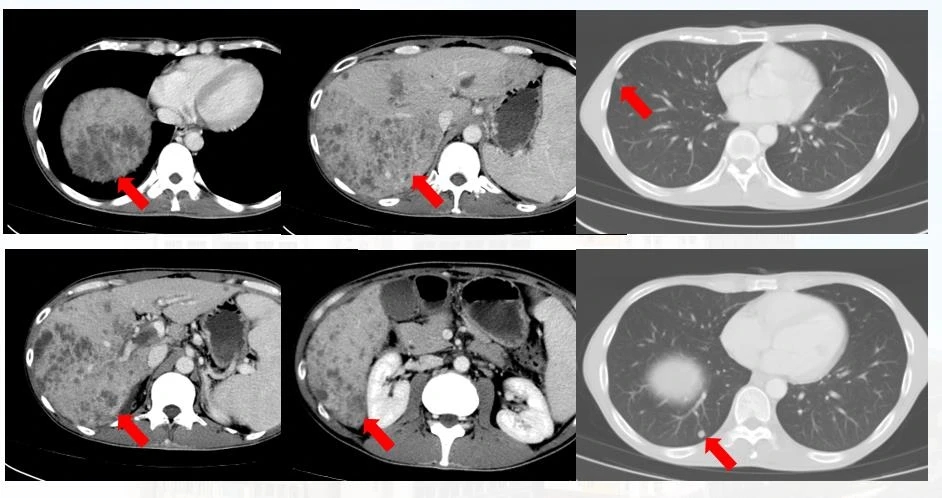

以赵言为例:

HAIC PD-1抗体动脉灌注 靶向治疗,第一个疗程后复查CT见上图( 2020-05-12 ),肝内及肺内病灶较前明显缩小。

第二个疗程后复查CT( 2020-06-12, 见上图)肝内病灶较前坏死增多,肺内病灶较前进一步缩小。